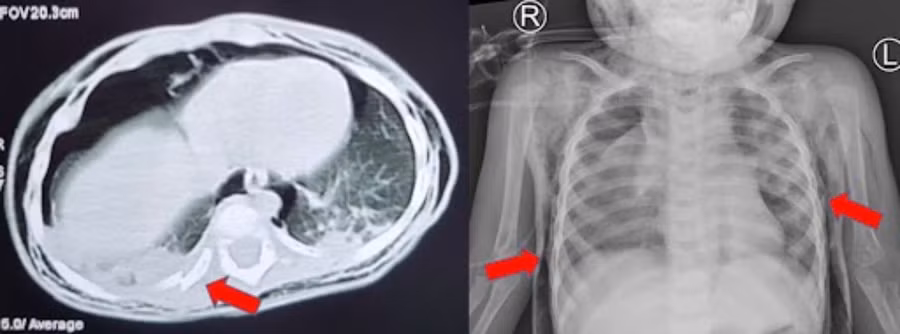

CT scan và Xquang phổi cho thấy trẻ bị tràn khí trung thất, tràn khí dưới da, gãy xương sườn. (Ảnh: BVCC)

Tại đây, sau khi hội chẩn chuyên khoa Hô hấp, Tai Mũi Họng, Hồi sức Ngoại, Gây mê hồi sức cùng, các bác sĩ chẩn đoán: P. vỡ khí quản, gãy xương sườn 8, 9, 10 (P), thống nhất xử trí mở ngực phẫu thuật tạo hình khí quản, nội soi phế quản kết hợp khi mổ.

Gần 2 tuần điều trị, tình trạng P. cải thiện, giảm dần tình trạng tràn khí trung thất và khí dưới da, cai máy thở, rút ống dẫn lưu màng phổi, tỉnh táo thở khí trời.